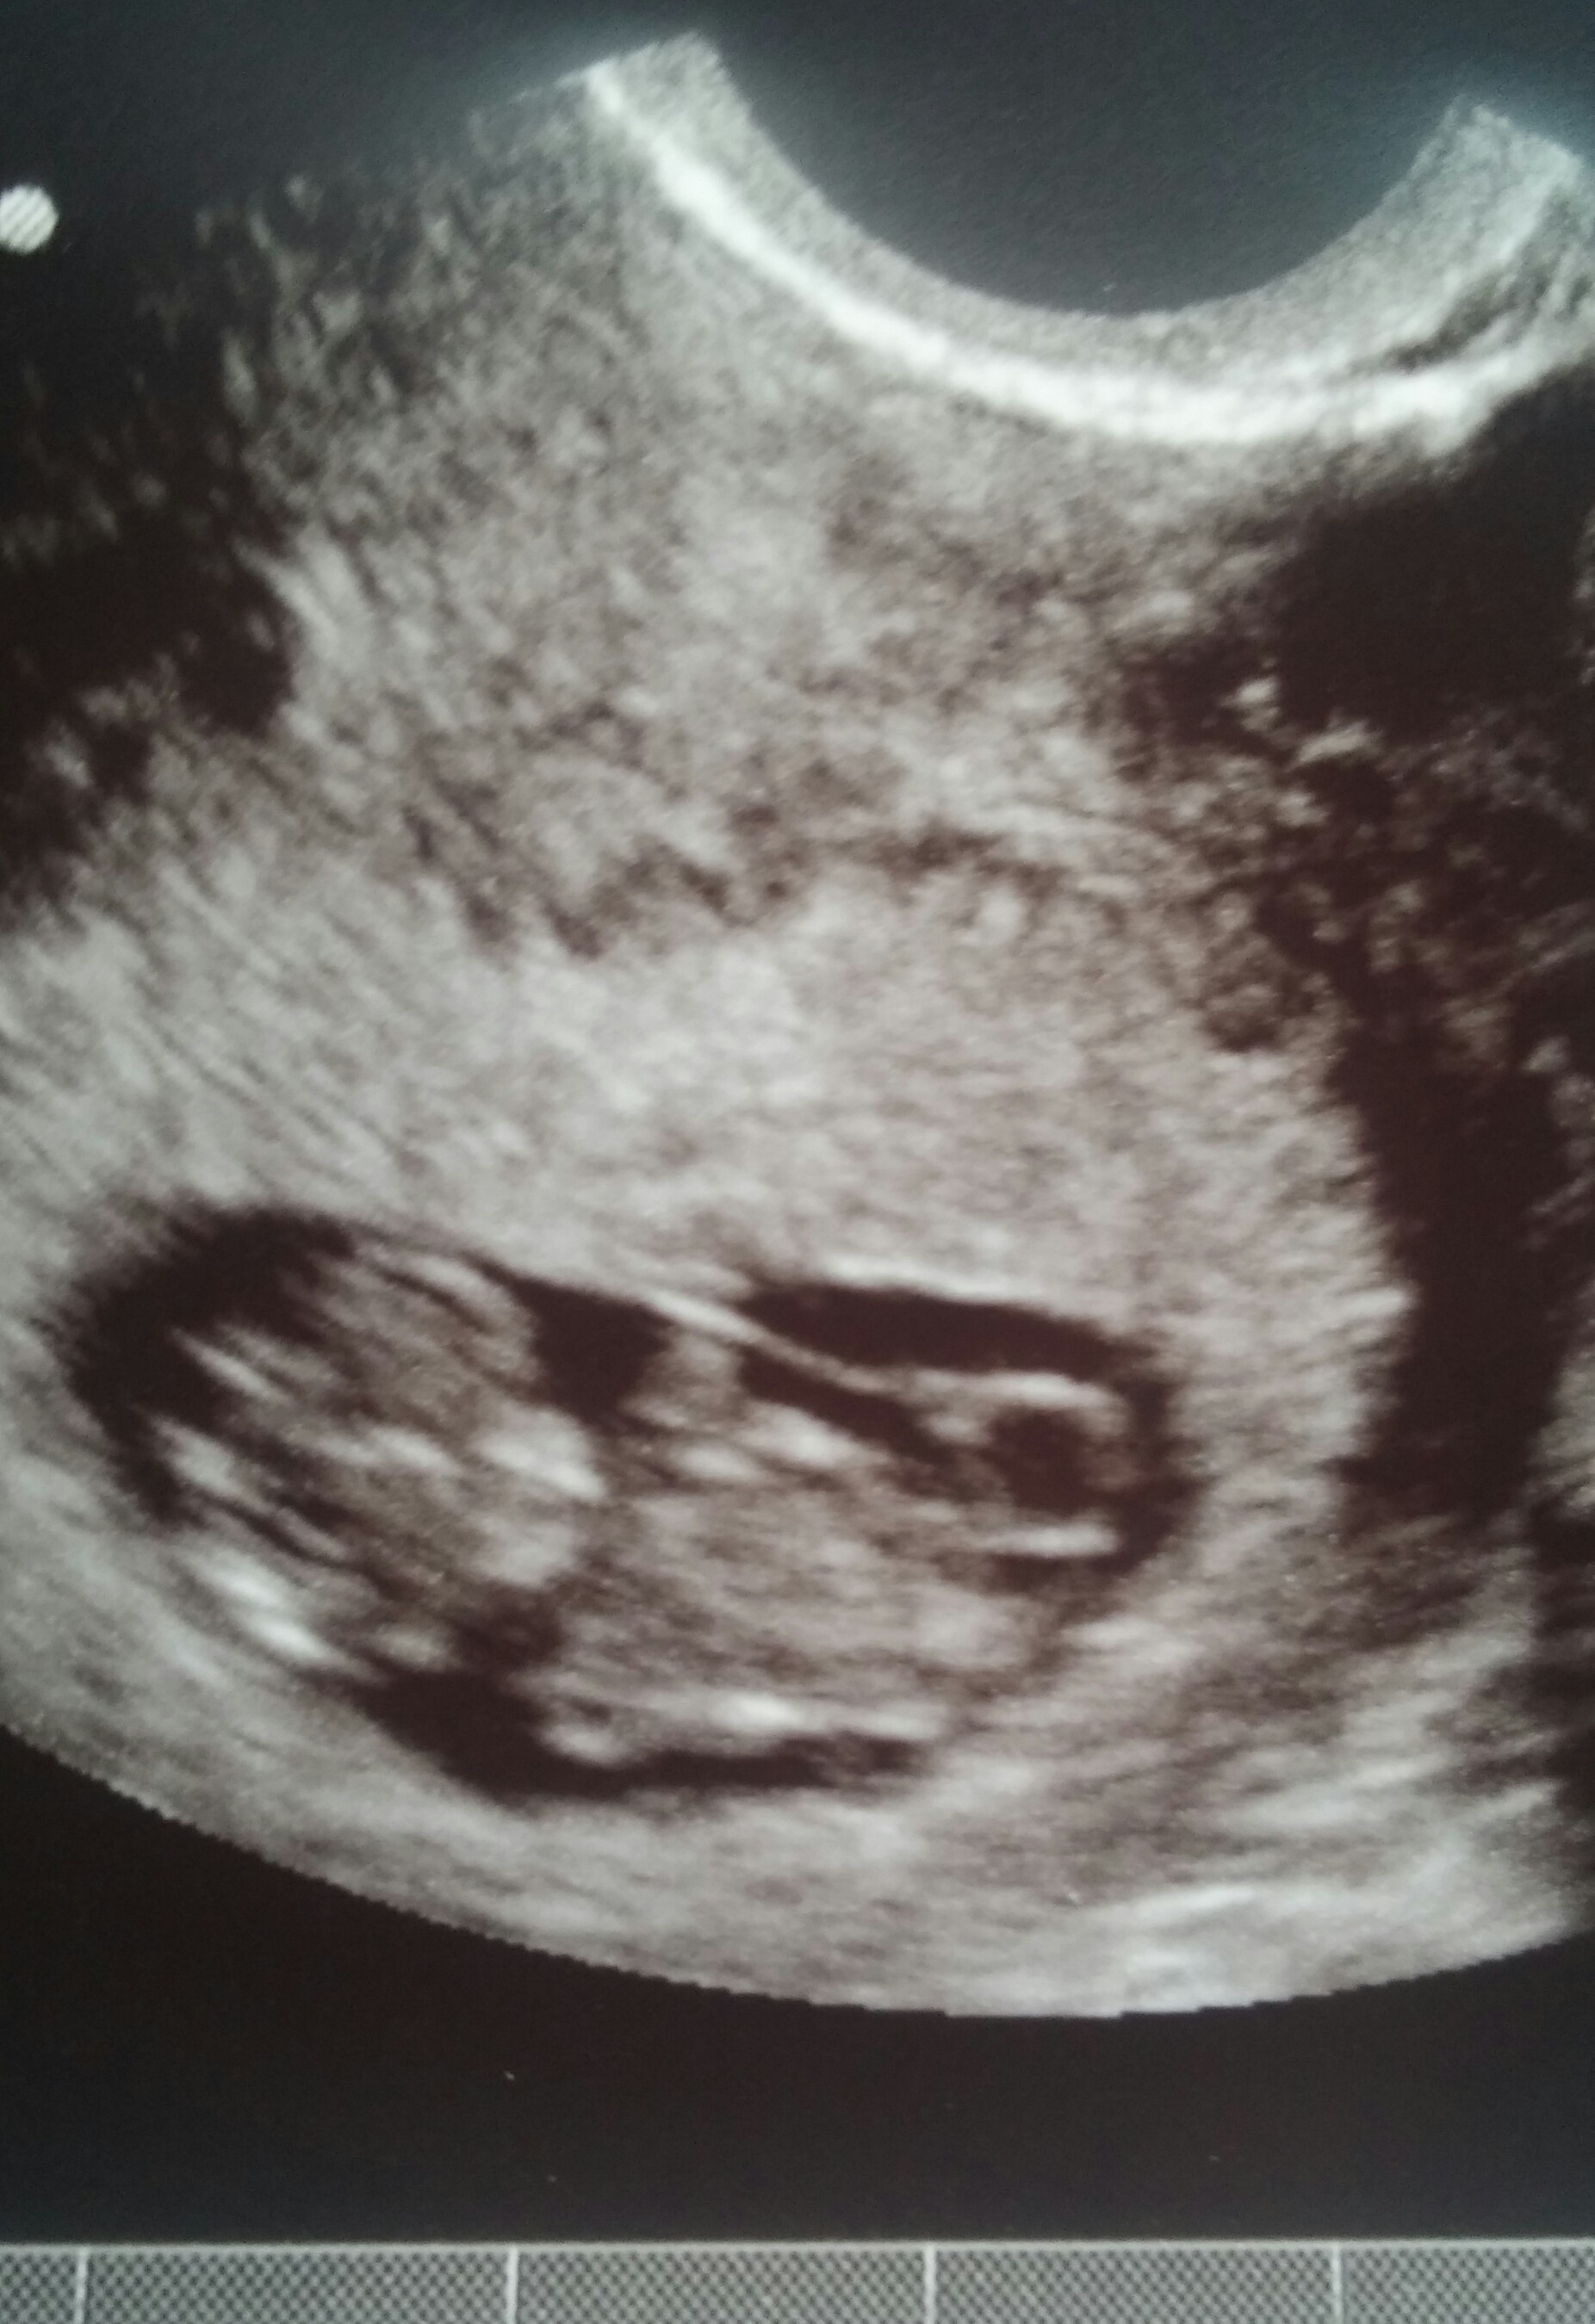

We had our NT scan today at 12w5d and the Doc said that everything looked great. My risk level is super low and it was absolutely amazing to see a baby in there instead of a blob!!! Baby was dancing around and kept it's hands near it's face for the most part. Here are two pics from the scan: